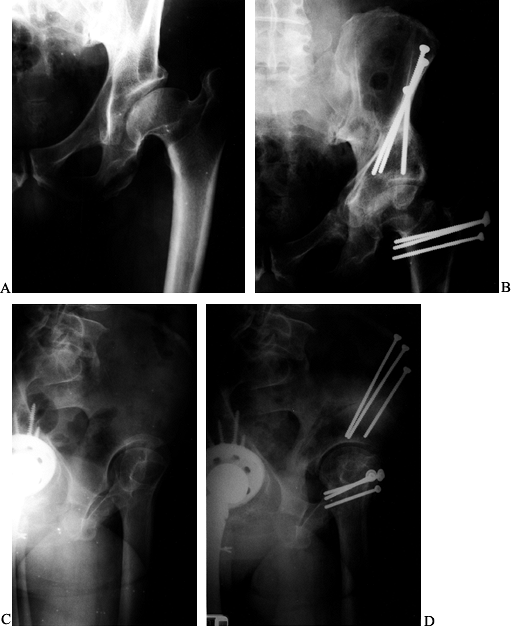

Figure 104.1.

Preoperative radiographic evaluation of the hip. This patient has avascular necrosis of the hip and is being evaluated for an intertrochanteric osteotomy. A: AP view. B: Frog-lateral view. C: AP view in adduction. D: Postoperative AP radiograph after valgus osteotomy. E: Postoperative lateral view. F: AP view after hardware removal showing good preservation of the joint space. G: Lateral view after hardware removal. |

Functional views of the hip with the femur in abduction and adduction

permit characterization of the joint space and demonstration of the

adequacy of motion in the required plane prior to any angular

intertrochanteric osteotomy (ITO) (Fig. 104.1A, Fig. 104.1C).

Performing these views under fluoroscopy is another alternative; this

can provide simultaneous information about the positions of relative

comfort. An AP radiograph with the hip in adduction and flexion

approximates the position of the joint after a valgus–extension ITO (Fig. 104.1C).